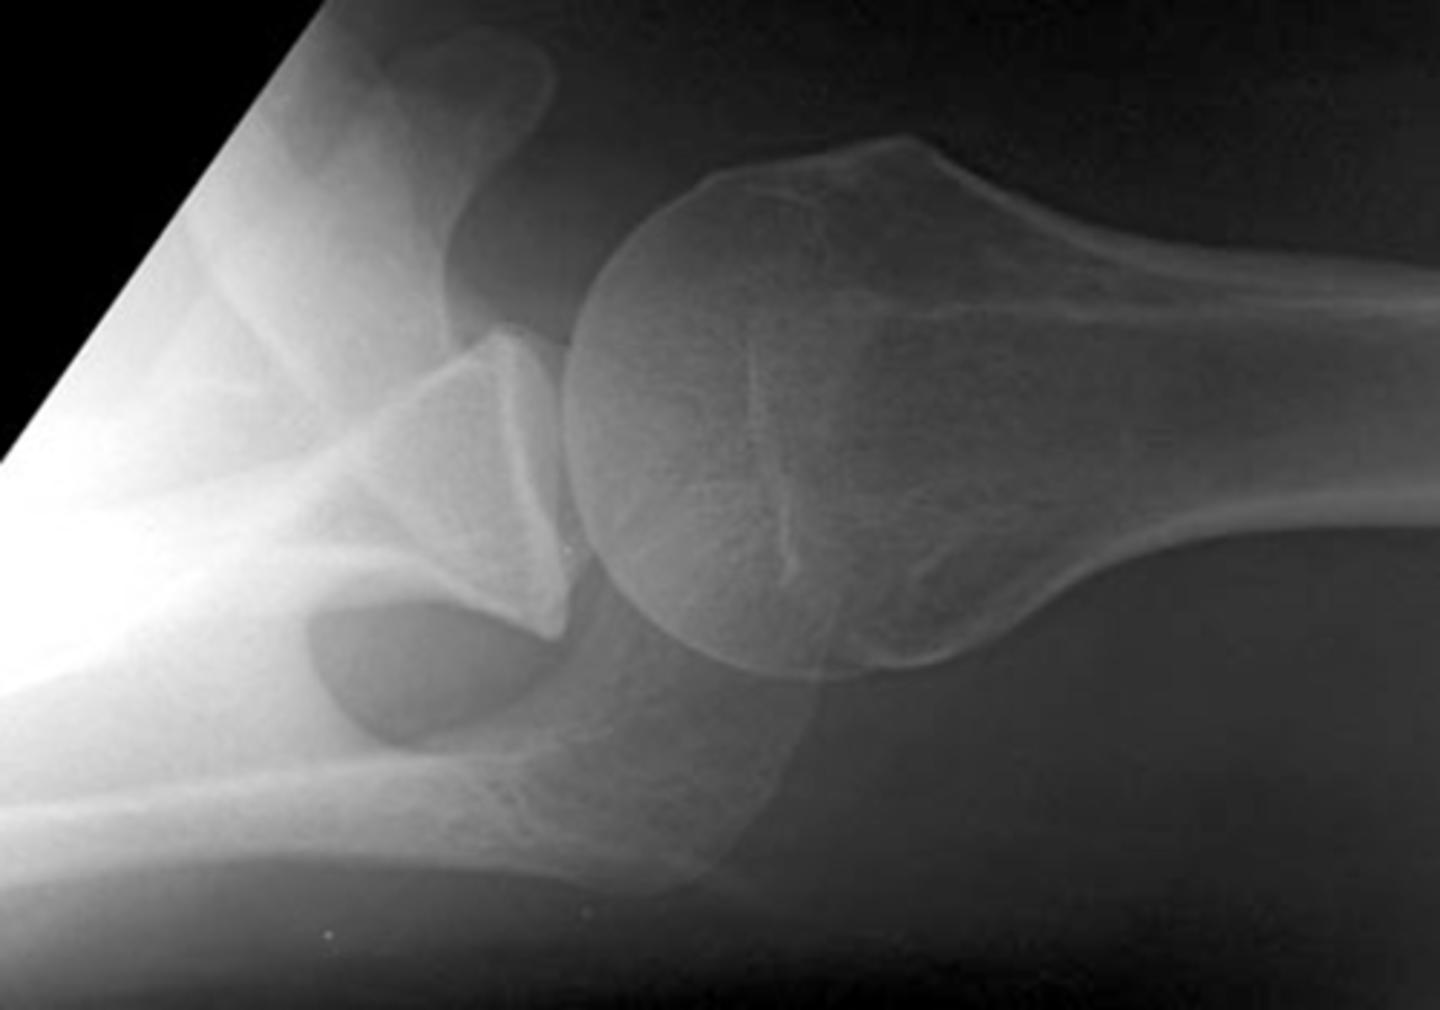

NOTE: this picture is an AXIAL view of the shoulder